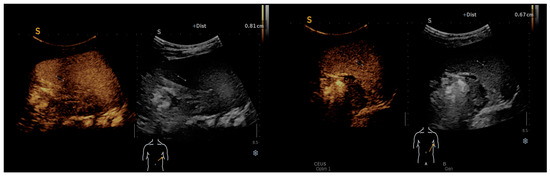

On imaging findings, we identified characteristic signs of systemic bartonellosis, as presented in Figure 2. The images revealed a profound impact of the infection across multiple organs. Specifically, Figure 2a demonstrates hepatic lesions that are distinguished by their central necrosis and surrounding diffuse edema, illustrating the severe effect of the infection on the liver. Figure 2b similarly depicts lesions within the spleen, following the same pattern of central necrosis enveloped by diffuse edema. These findings underscore the extensive reach of bartonellosis within the patient, affecting not only the liver and spleen but also extending to the skeletal system, including the right iliac bone, femoral neck, pubic bone, and L1–L2 vertebrae.

Figure 2. (a) Hepatic lesions with central necrosis and diffuse edema; (b) spleen lesions with central necrosis and diffuse edema.